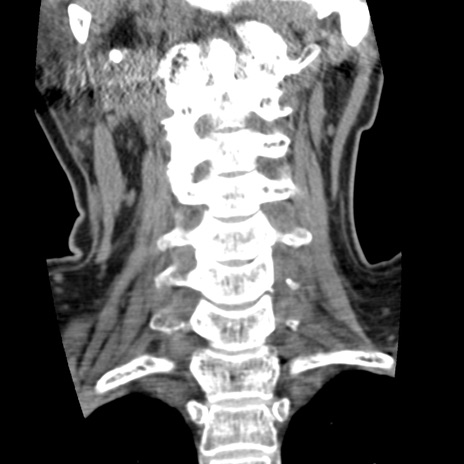

症例50 頚椎CT(冠状断像)

【症例】60歳代女性

【主訴】後頭部〜右後頸部にかけての痛み

【現病歴】本日飲食店でコーヒーを飲んでいたところ、突然後頭部〜右後頸部にかけて痛みが出現し、右上肢の感覚障害を伴ったため救急要請。

【身体所見】脳神経学的に明らかな異常所見を認めず。右上肢に軽度の感覚障害あり。

異常所見と診断は?